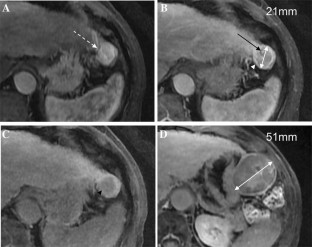

The Liver Imaging Reporting and Data System (LI-RADS) was designed to standardize the interpretation and reporting of observations seen on studies performed in patients at risk for development of hepatocellular carcinoma (HCC). The LI-RADS algorithm guides radiologists through the process of categorizing observations on a spectrum from definitely benign to definitely HCC. Major features are the imaging features used to categorize observations as LI-RADS 3 (intermediate probability of malignancy), LIRADS 4 (probably HCC), and LI-RADS 5 (definite HCC). Major features include arterial phase hyperenhancement, washout appearance, enhancing capsule appearance, size, and threshold growth. Observations that have few major criteria are assigned lower categories than those that have several, with the goal of preserving high specificity for the LR-5 category of Definite HCC. The goal of this paper is to discuss LI-RADS major features, including definitions, rationale for selection as major features, and imaging examples.

Fig. 3